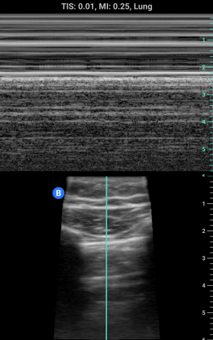

M-mode: Motion-mode or M-mode is another common image mode. M-mode creates an image by plotting the signal from one single ultrasound beam over time. It is used commonly in cardiac ultrasound for showing the movement of heart valves or visualizing lung sliding.